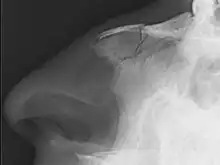

| Plain X-ray showing a nasal fracture | |

| Diagnostic method | Typically based on symptoms, occasionally plain X rays[1] |

Nasal fractures are usually identified visually and through physical examination.[1] In addition, relevant questions to ask the patient include whether there is a noticeable cosmetic deformity and whether the patient has difficulty breathing through the nose after the injury. Medical imaging is generally not recommended.[1][3] A priority is to distinguish simple fractures limited to the nasal bones (Type 1) from fractures that also involve other facial bones and/or the nasal septum (Types 2 and 3). In simple Type 1 fractures X-Rays supply surprisingly little information beyond clinical examination. However, diagnosis may be confirmed with X-rays or CT scans, and these are required if other facial injuries are suspected.[3]